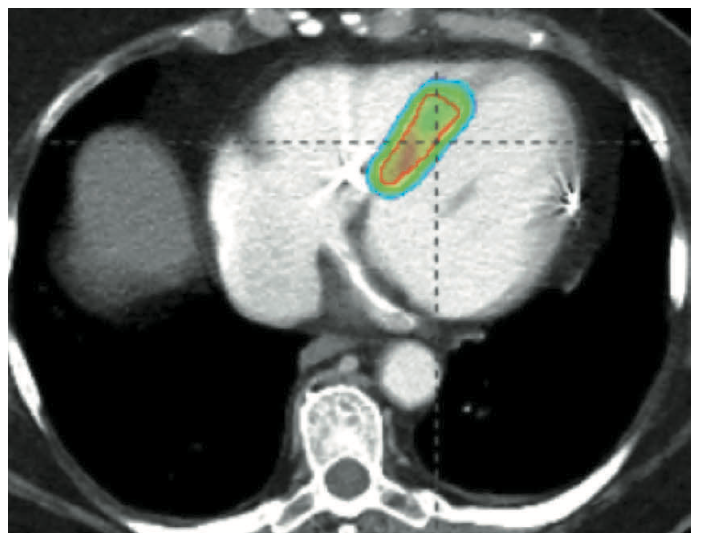

Catheter-based RF ablation remains the gold standard for the treatment of VT.10 Patients with refractory VT may fail traditional therapy due to inaccessible substrate or high-risk comorbidities precluding repeat ablation. SBRT (or stereotactic ablative radiotherapy) is a method commonly used in the treatment of solid tumors for precise delivery of radiation to tissue, with minimal interaction to adjacent tissue.11 In the first case series, Cuculich et al described use of SBRT (described as cardiac radioablation [CRA]) targeting myocardium by coupling noninvasive electroanatomic mapping with electrocardiographic imaging and multimodality imaging, including computed tomography, transthoracic echocardiography, and cardiac magnetic resonance imaging to precisely localize VT substrate in 5 high-risk patients with refractory VT.12 A dose of 25 Gy ionizing radiation in a single fraction was prescribed over the total targeted volume (Figure 6).12 Following therapy, there was a reduction from 6577 events to 4 events.11 This novel approach led to the prospective phase I/II ENCORE-VT trial demonstrating efficacy with a 97% reduction in ICD shocks and antitachycardia pacing, and improved quality of life. This therapy is thought to be easier on patients; it lasts 5-10 minutes and treatment occurs while the patient is awake, free-breathing, and listening to music. Because it is entirely noninvasive, there have been no procedural adverse events. In some centers, patients are now treated as outpatients after a 10-minute treatment.